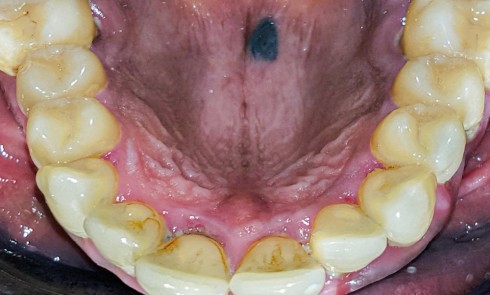

Article réservé à nos abonnés Découverte fortuite d’une coloration palatine

Situation clinique Anamnèse. Un patient adulte est adressé par son chirurgien-dentiste traitant après la découverte fortuite d’une lésion palatine. Il...